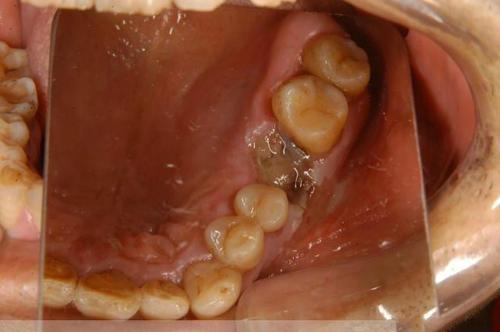

(1) Bei frühem Zahnfleischkrebs treten Geschwüre am Zahnfleischrand und schmerzhafte Symptome auf, die oft mit Parodontitis oder Gingivitis verwechselt werden und nicht leicht zu unterscheiden sind, so dass wir darauf achten müssen, sie zu beobachten und die Wachsamkeit zu erhöhen.

(2) Die klinischen Symptome in der mittleren Phase können Zahnfleischbluten, Zerstörung der Knocheninfiltration und einige lockere und schmerzhafte Zähne umfassen. Zu diesem Zeitpunkt sind die Symptome in der Regel ausgeprägter, wir müssen zahnärztliche Bildgebung wie Röntgenstrahlen, wenn nötig, auch tun müssen, pathologische Bilder, um die Diagnose weiter zu klären.

Ein frühes Gingivakarzinom, insbesondere wenn es auf den Zahnfleischrand oder die Interdentalpapillen beschränkt ist, wird leicht als Gingivitis oder Parodontitis fehldiagnostiziert; zweitens können frühe ulzerative Läsionen, insbesondere diffuse Zahnfleischränder, die von Schmerzen begleitet sind, auch als Gingivatuberkulose fehldiagnostiziert werden. Bei der klinischen Diagnose der oben genannten Krankheiten sollte auf die Möglichkeit eines Gingivakarzinoms geachtet werden, und die Röntgenuntersuchung zeigt eine "fächerförmige" Zerstörung des Kieferknochens mit wurmartigen Rändern.

Zahnfleischkrebs wächst im Frühstadium langsam und äußert sich in der Regel durch die Bildung von Geschwüren oder nach außen gewölbten Wucherungen, die Symptome wie Zahnfleischschmerzen und lockere Zähne verursachen können.

Zahnfleischklumpen und -geschwüreKlumpen können im Bereich des Zahnfleisches ertastet werden, und es können Geschwüre am Zahnfleisch und in den angrenzenden Bereichen auftreten.

Schmerzhaftes, blutendes ZahnfleischDie Patienten haben oft Schmerzen im Zahnfleischbereich und ihr Zahnfleisch blutet leicht.

loser ZahnDie Patienten können eine Lockerung, Verschiebung oder sogar den Verlust von Zähnen im entsprechenden Bereich der Krebsherde feststellen. Wenn der Zahn gezogen wird, kann man sehen, dass die Wunde nicht heilt, was dazu führt, dass sich weitere Zähne lockern oder aufschwimmen.